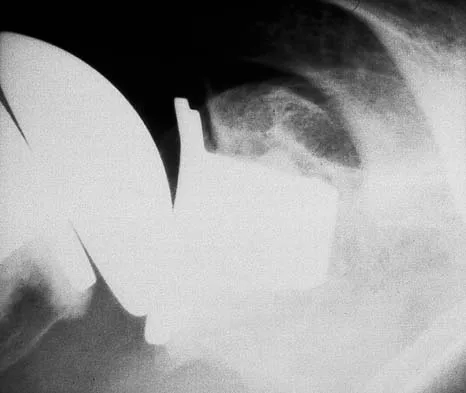

Question 75

A 45-year-old woman has had progressive right shoulder pain for the past 6 months. She notes that the pain disrupts her sleep, she has pain at rest that requires the use of narcotic analgesics, and she has limited use of her left shoulder for most activities of daily living. History reveals the use of corticosteroids for systemic lupus erythematosus. Examination shows diminished range of motion. Radiographs of the right shoulder are shown in Figures 4a and 4b. Treatment should consist of

Explanation